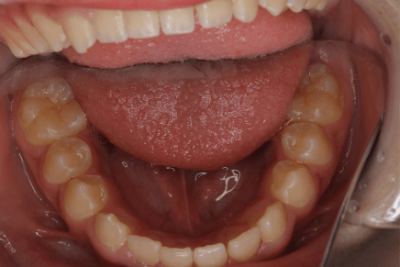

写真①:使用する装置例

写真①の装置を就寝時に使用することでこれらを改善していきます。